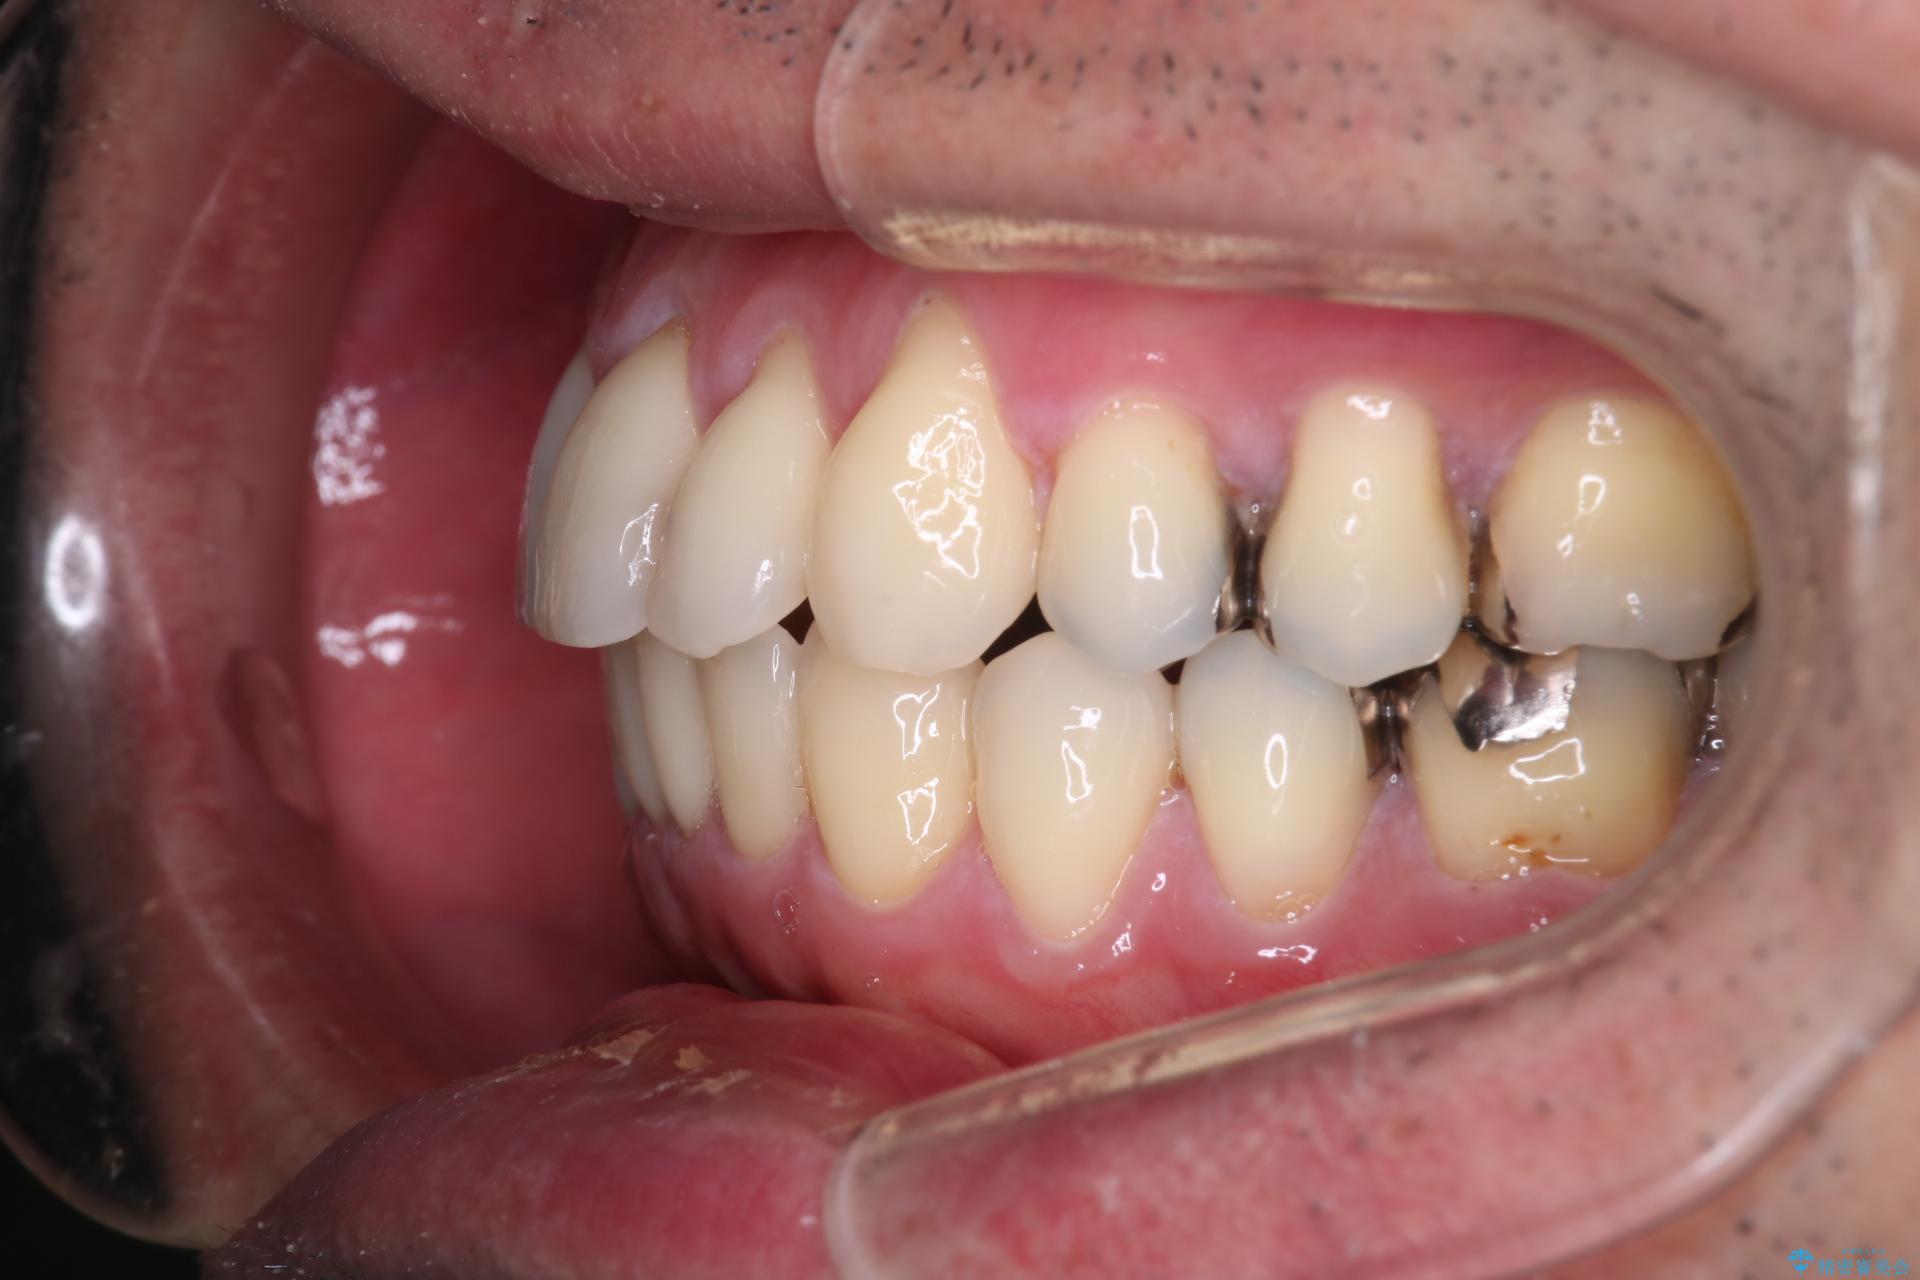

- 右上2番目の歯が舌側転位していることと前歯の叢生(がたつき)を主訴に来院されました。

右上の犬歯が初診時よりかなり歯根露出しており、矯正の力をかけるとさらに歯根露出するリスクがあるため、右上の2番目の歯を前に出すためにも

右上の犬歯を抜歯して歯並びを整える治療計画を立てました。